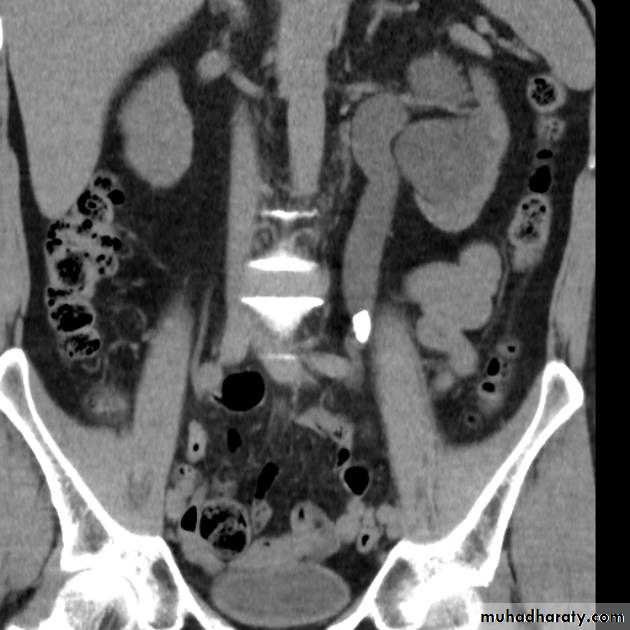

Now CT scans used during acute renal stone-Non contrast CT sensitively identify calculi and non opacified collecting system down to the level of obstruction. it has a sensitivity of 97% and specificity of 96% for detection of ureteral calculi

Poly cystic disease

Adult typePresent after the third decade of life , Familial.

Renal parenchyma is replaced by numerous cysts containing fluid , The cysts are of variable size ,

Clinically renal colic, loin mass , heamaturia and hypertension, Renal tissue interposed between the cysts after time dssimcted ended with renal failure

Almost bilateral.

IVU

Large kidney .

Lobulated out-line.

Distortion of pelvi- calyceal system depend on cyst size, number and position.

In advanced cases there is elongation and stretching of minor and major calyces ( spider leg).

In advanced cases IVU shows non-functioning kidney .